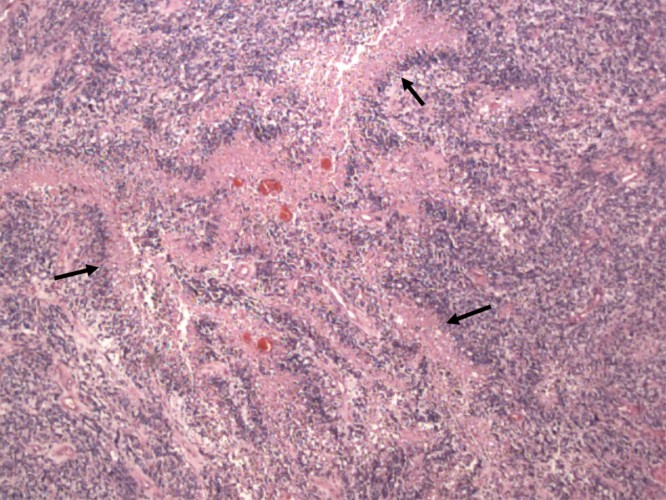

- Pathology: Cells with increased mitotic activity with pseudopalisading necrosis and microvascular endothelial proliferation.